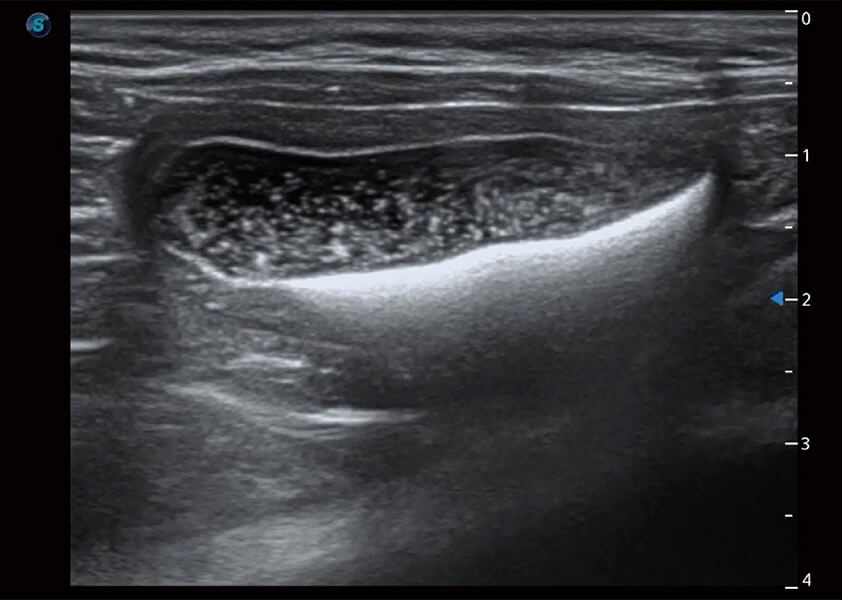

ProPet 60 作为一款高端台式动物超声设备,为动物医生的日常诊断提供了一系列贴合动物临床需求、解决临床实际问题的高级成像功能。凭借全系列高清探头,满足医生对腹部、心脏、生殖、浅表、肌骨等成像的所有需求,切实帮助您提升检查效率,提高诊断信心。

动物是人类最亲密的朋友和最值得信赖的伙伴。新葡的京集团8814检测站也一直致力于探索动物专用的超声影像解决方案。 全新推出的ProPet系列,是新葡的京集团8814检测站在动物超声影像智能化、专业化、精准化的一次跨越式革新。动物不能用言语来表述自己的不适,通过超声影像,ProPet系列搭建了动物医生与不同物种沟通的“桥梁”,为动物医生注入了“治愈之力”。